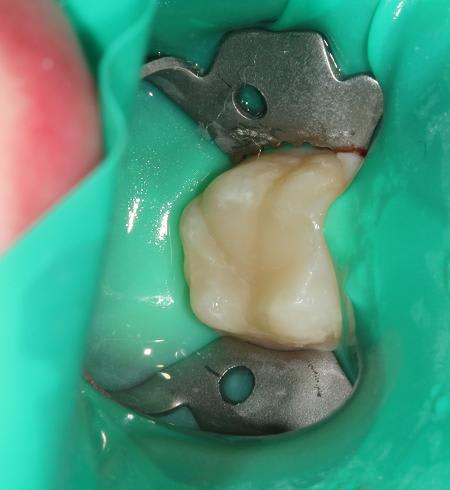

Quelques photos pour illustrer le sujet initial. Dommage que ces dents n'aient jamais eu de sealants.

Pour l'effraction pulpaire sur dent asymptomatique, je fais le protocole que Choixpeau avait mis sur le forum : hypochlorite puis adhésif directement au contact. Aucun problème à court terme pour le moment.

Si effraction plus importante : MTA.